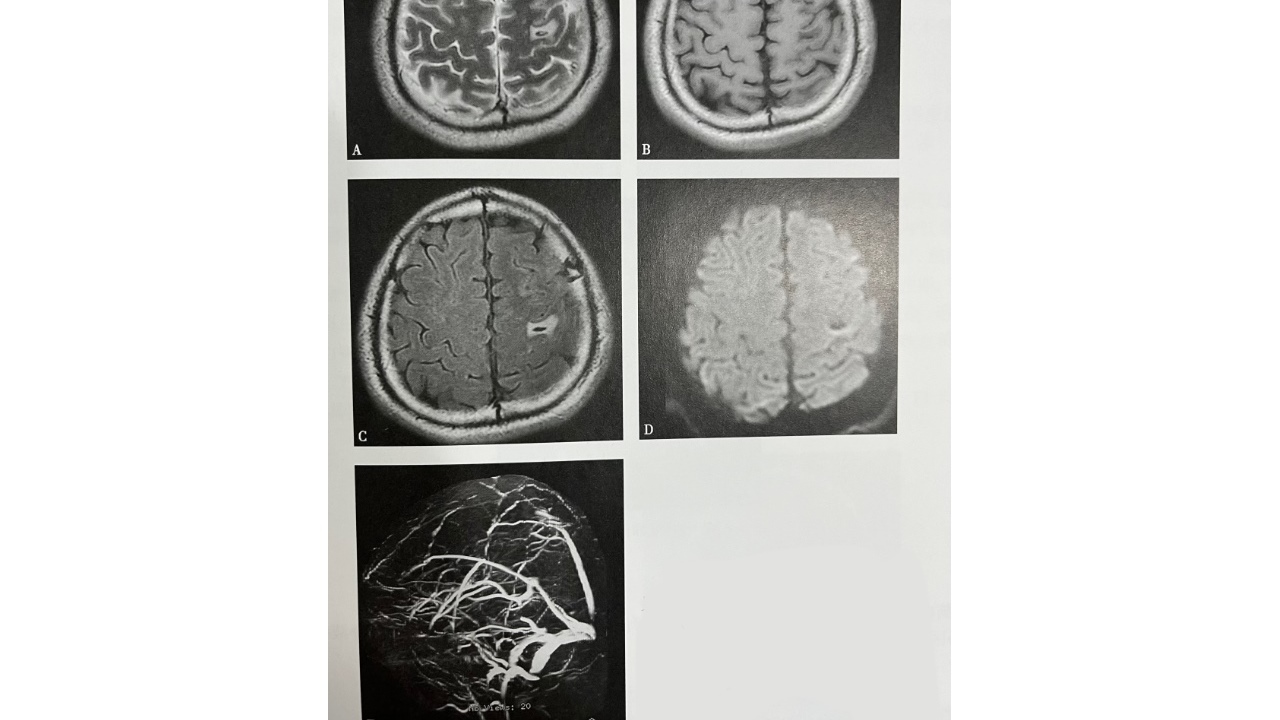

图5.左侧额叶脑梗死并出血

A~D(A.T2WI,B.T1WI,C.T2WI-FLAIR,D.DWI):左侧额叶可见片状等长T1长T2信号灶,最大截面约15mmx16mm,局部可见斑条状短T1信号灶